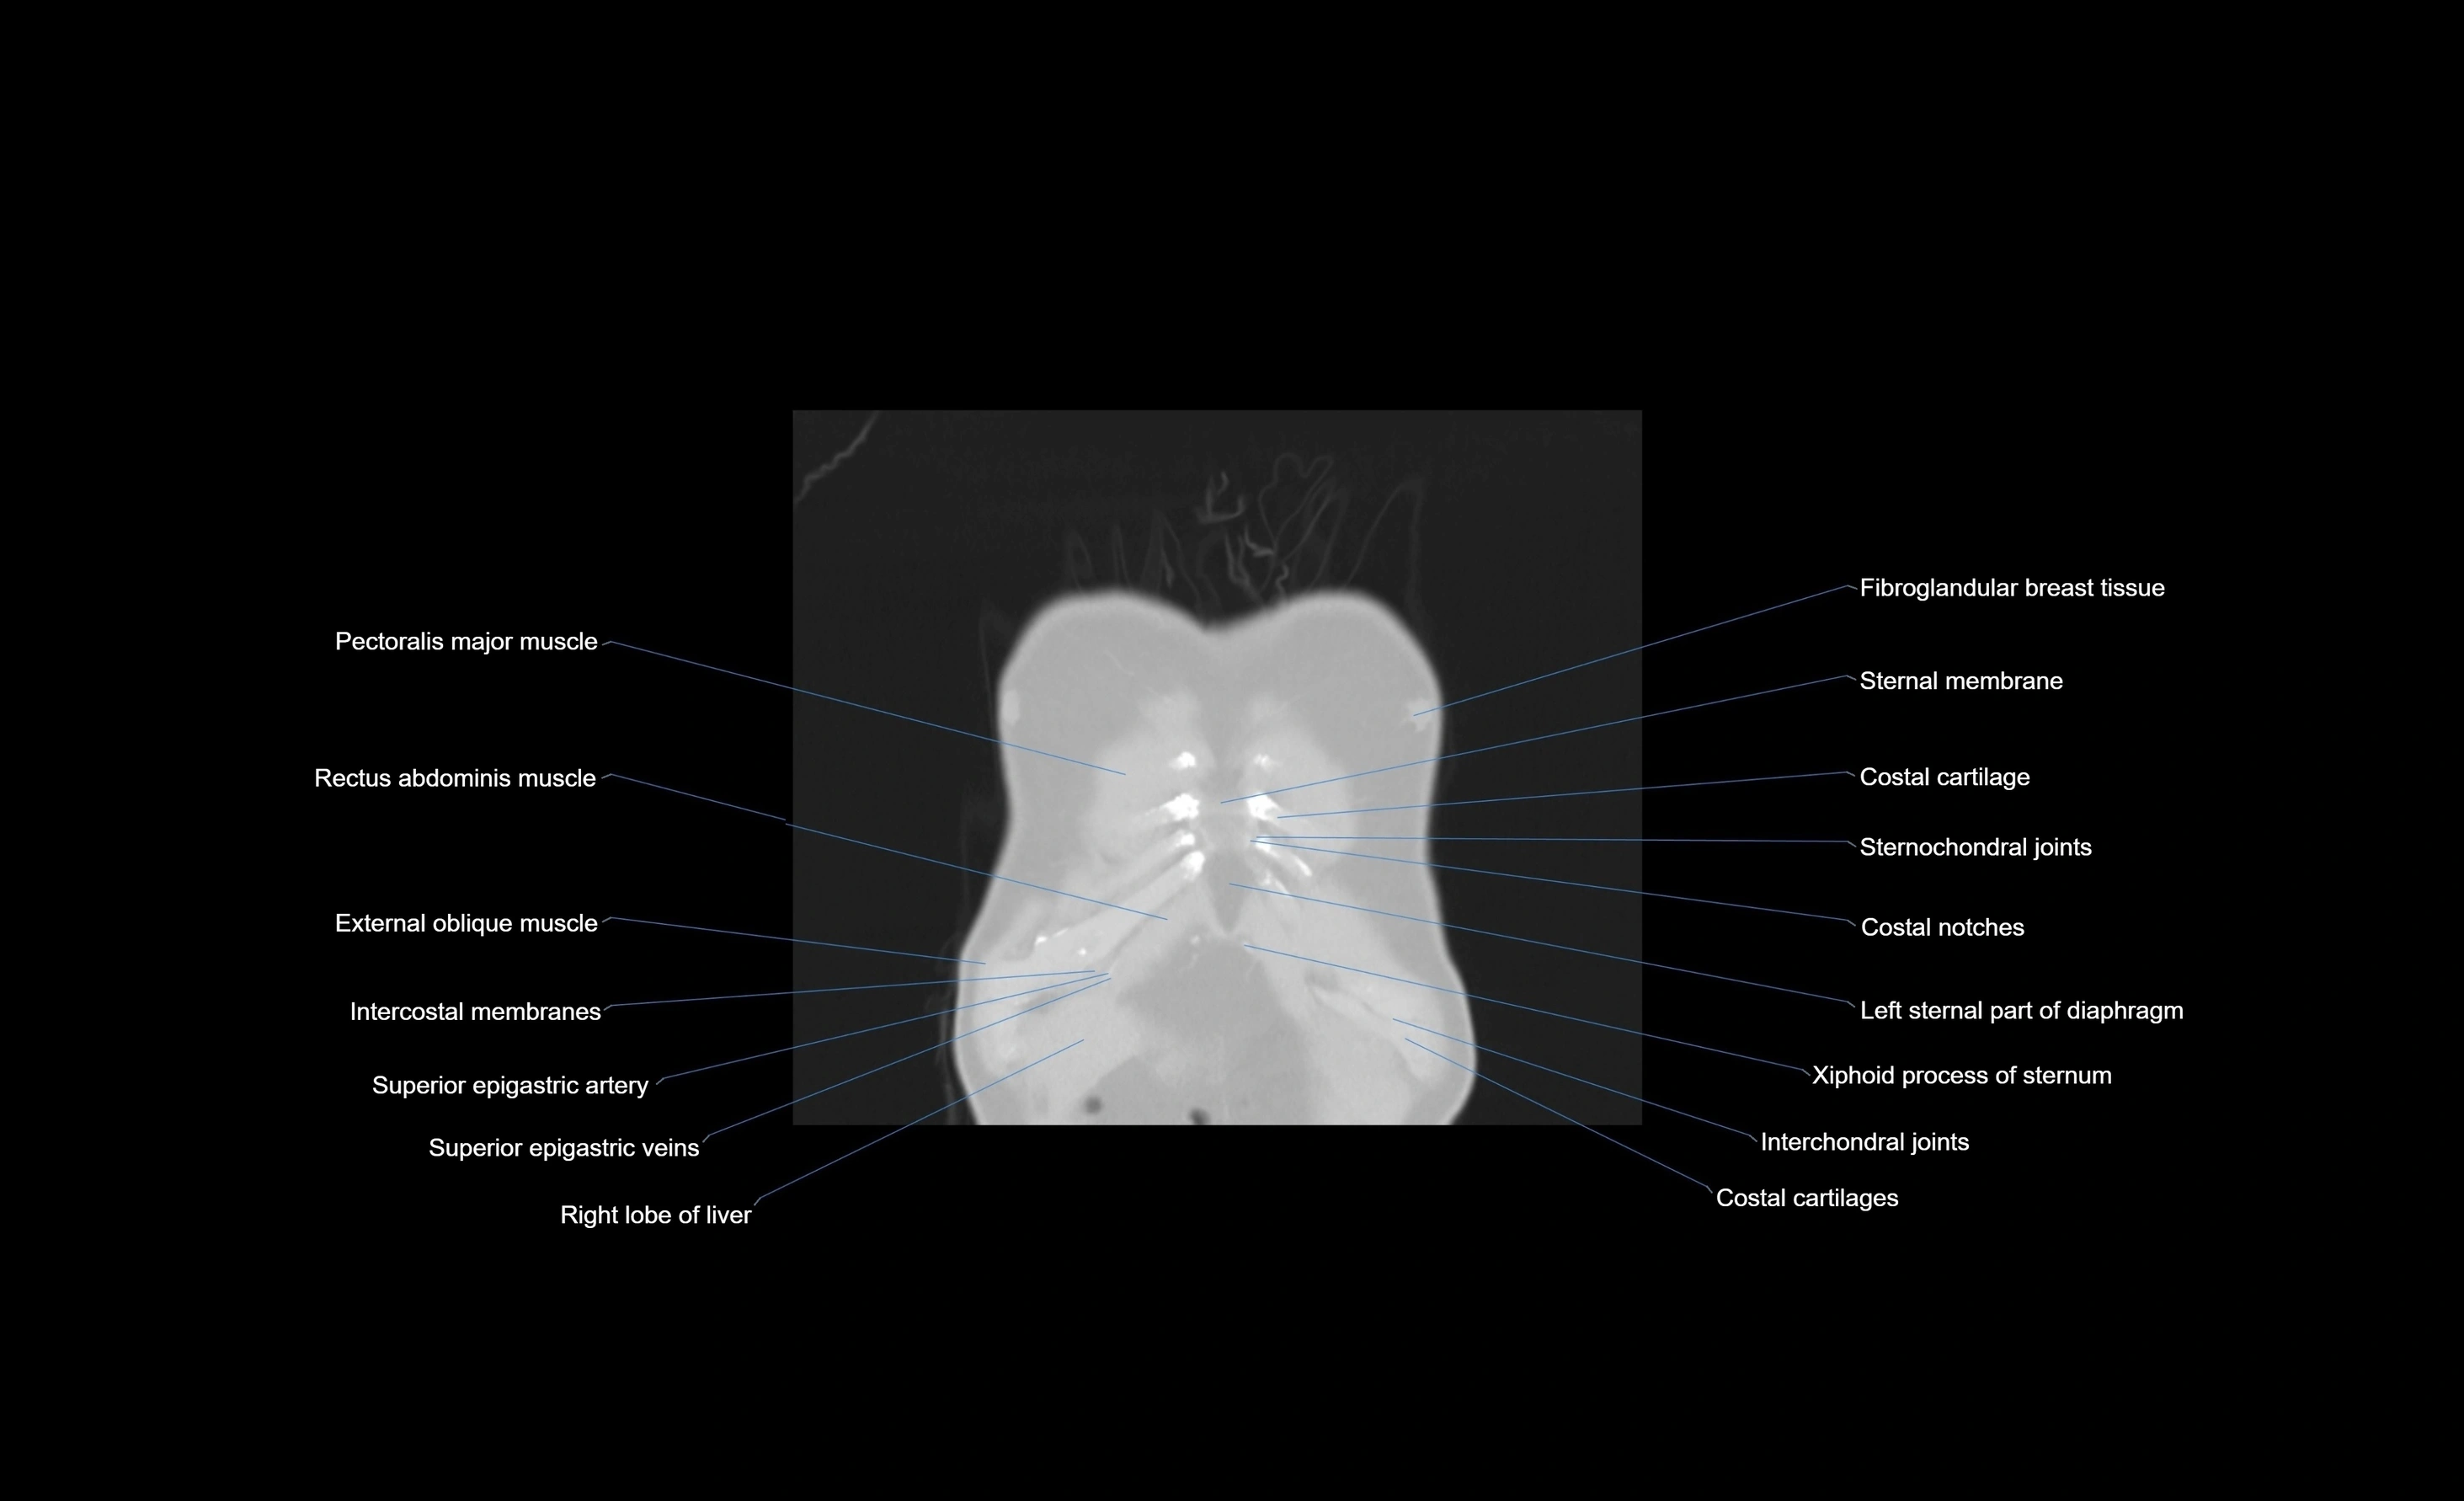

MRI images